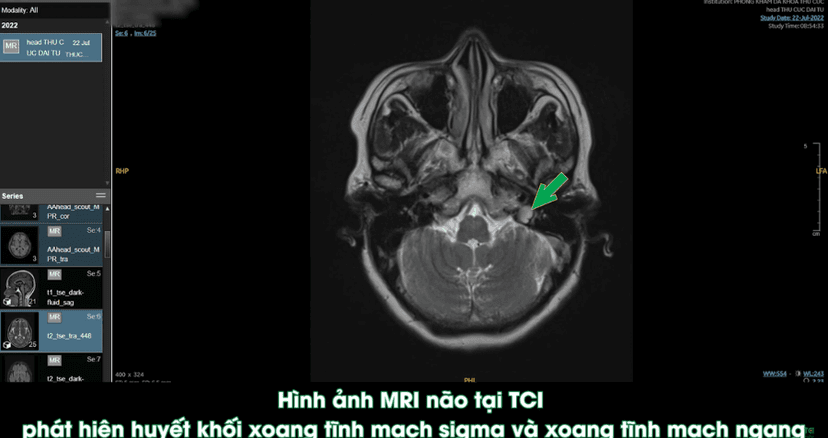

Huyết khối tĩnh mạch – Cục máu đông tĩnh mạch não nguy hiểm